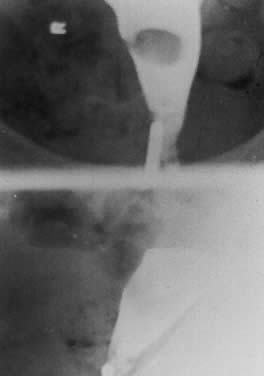

Appraisal of the endometrial cavity is best done by sonohysterography, hysterosalpingography (Fig. 6), or hysteroscopy. In patients who are bleeding heavily, the hemoglobin level should be followed, because it is easy for patients with bleeding uterine myomas to develop iron-deficiency anemia. It is also advisable to check the stool guaiac in the patient who is anemic and reports abnormal vaginal bleeding to exclude occult gastrointestinal bleeding. The combination of abnormal vaginal bleeding and uterine fibroids is so common that the examiner occasionally misses the diagnosis of occult gastrointestinal bleeding by focusing on the patient's history and not excluding other serious causes of anemia in the middle-aged woman.

Fig. 6. Submucous myoma presenting as menorrhagia and anemia.